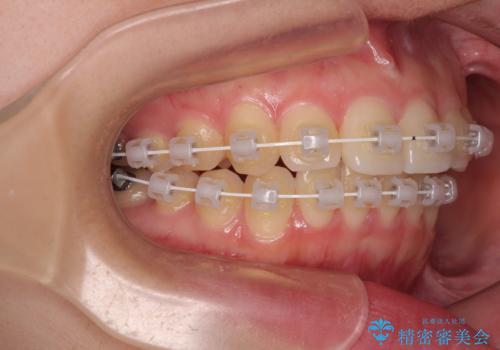

- 矯正装置

- 審美装置

ワイヤー矯正でもマウスピース矯正でも可能でしたが、短期間で、自身の手を煩わせることなく治療を行いたいとのことで、ワイヤー装置にて矯正治療を行うこととしました。